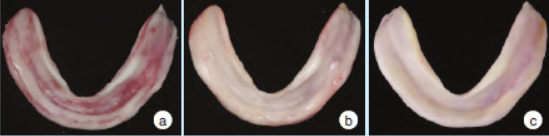

2.2义齿组织面、咬合印迹、哥特式弓描记图像和黏膜状态变化

治疗性义齿组织面呈现的变化规律:组织调理剂逐渐分布均匀,下颌义齿唇颊侧边缘向外扩展,舌侧适应性变化(图3)。咬合印迹变化:逐渐对称、均匀,呈明确的点接触,无早接触,无滑动(图4)。

图3 治疗前后义齿组织面变化

哥特式弓描记图像变化:若下颌运动轨迹从圆顶型、偏侧型或多顶点型转变为尖顶型,说明关节、神经和肌肉都逐渐稳定(图5)。口内黏膜变化:经治疗后,口内的黏膜逐渐由红肿、溃疡的状态,转变为健康的状态(图6)。

图6 治疗前后口内黏膜变化